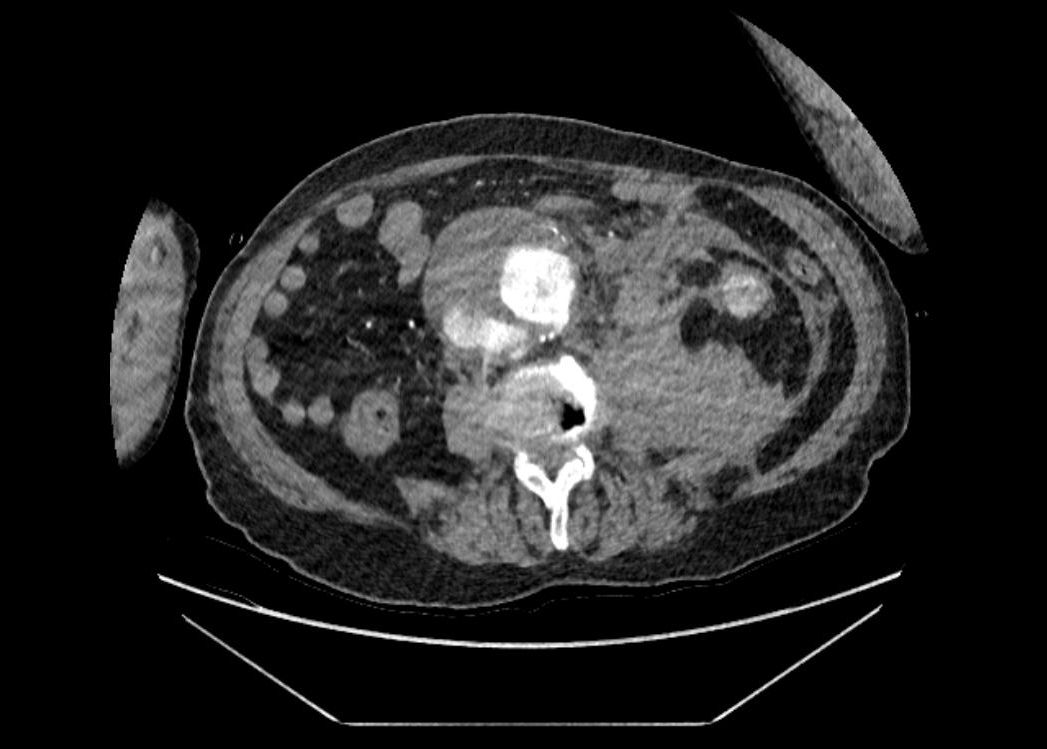

Pruebas complementarias: TC toracoabdominal: extenso hematoma retroperitoneal secundario a rotura de aneurisma de aorta abdominal infrarrenal (AAA) de 8,1 cm con extensión craneocaudal de 10 cm con trombo mural.